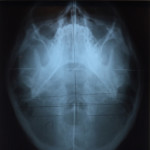

If it’s your first time to go to an upper cervical chiropractor, you’ll need an average of 8 to 12 visits, then the doctor will re-assess you for lifetime treatment. The first session involves a general assessment of your health, habits, and posture, followed by three x-rays (from the side, front, and top of head and neck) specific to the practice of upper cervical chiropractic. This is usually the longest session. The doctor will then study your x-rays, posture, and result of the initial consultation, and based on all these will determine if you need an atlas or spine adjustment on your next visit.

Top of head